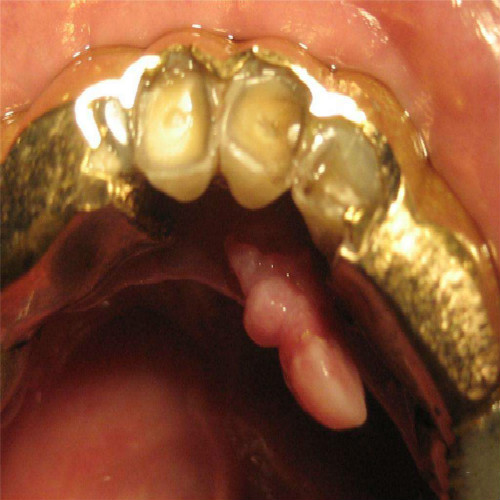

牙齦息肉症狀

牙齦息肉

牙齦息肉的